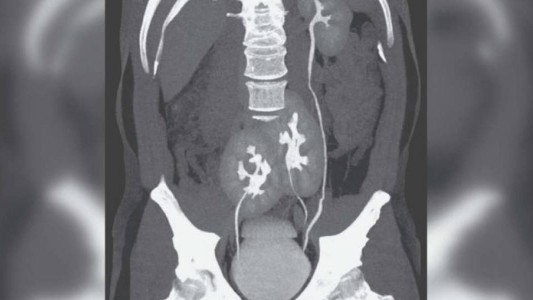

Fue al hospital por un dolor de espalda y descubrieron que tenía tres riñones